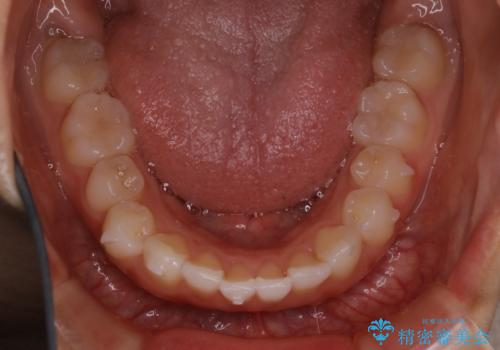

前歯のがたつきをインビザラインで治療

- 上下前歯のがたつきが気になるとの事で来院された患者様です。がたつきの程度が軽度であったため、インビザラインライトにて治療をおこないました。

がたつきの程度が軽度であったことと、インビザラインを正しく装着して頂けたことで短期間で治療終了することが出来ました。